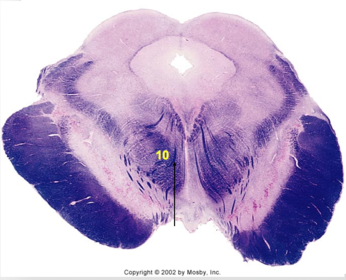

| Nucleus gracilis | |

| Accessory nucleus | |

| Medial longitudinal faciculus | |

| Pyramidal decussation | |

| Medullary pyramids | |

| Anterior spinocerebellar tract | |

| ALS | |

| Posterior spinocerebellar tract | |

| Spinal tract of V | |

| Spinal nucleus of V | |

| Nucleus cuneatus | |

| Fasciculus cuneatus | |

| Fasciculus gracilis | |

| Central canal | |

| Internal acruate fibers | |

| Lateral (external/accessory) cuneate nucleus | |